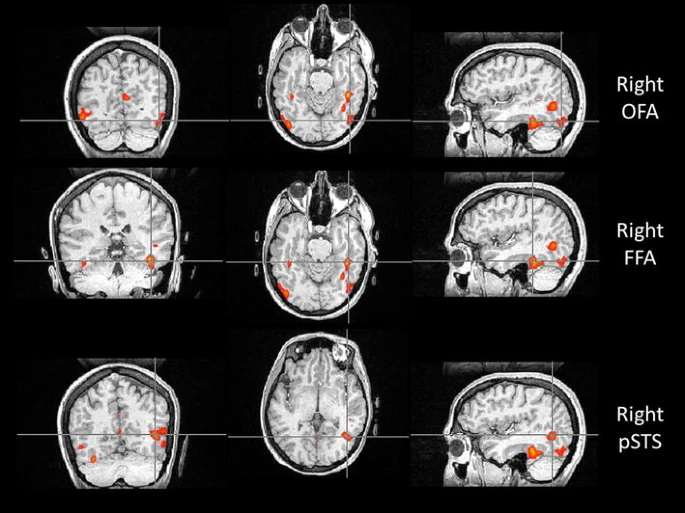

比如,位于枕叶的枕叶面孔区(Occipital Face Area, OFA),就像识脸网络的“先锋部队”。它专门处理眼睛、鼻子和嘴巴等五官“零部件”。当一张脸出现在我们眼前时,OFA 只需 约 100 毫秒 就能被激活,迅速对局部特征进行拆解,并将信息传递给 FFA 和上颞沟(Superior Temporal Sulcus, STS)。所以如果 OFA 出现问题,识别人脸就会变得很困难。

与认脸有关的三个核心脑区,自上而下依次为:OFA(枕叶面孔区)、FFA(梭状回面孔区),以及 STS(上颞沟)。本文图片均来自中国科协科普部综合